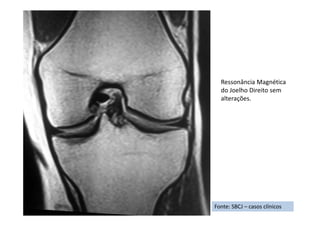

Sinovite vilonodular pigmentada difusa

• Resumo do caso: Recidiva de sinovite vilonodular pigmentada após ressecção